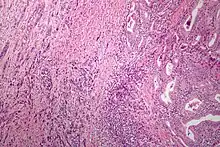

| Microscopic image of anaplastic thyroid carcinoma. H&E stain. | |

Anaplastic tumors have a high mitotic rate and frequently invades the local blood and lymphatic vessels.[5] Cellular death is frequently visualized on microscopic images.[2] The presence of regionally swollen lymph nodes in older patients in whom needle aspiration biopsy reveals characteristic vesicular appearance of the nuclei supports a diagnosis of anaplastic carcinoma. Microscopic images of ATC usually show inflammatory cells from the immune system such as T cells and macrophages.[2]

ATC is divided into several different subclasses based on its microscopic characteristics. These include sarcomatoid, squamoid, osteoclastic, paucicellular, rhabdoid, and carcinomasarcoid variants.[2] As of 2019, despite the fact that these ATC subtypes are recognized, this classification has not led to differences in management.[2] ATC is always considered to be stage IV when it is diagnosed.[6]